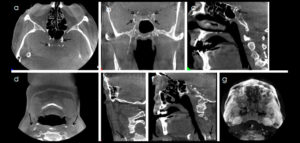

91- Anquilosis de la articulación temporomandibular como una complicación de la artritis séptica neonatal

La artritis séptica es una infección purulenta de alguna articulación, la cual se produce cuando los microorganismos invaden el espacio de alguna articulación, ya sea